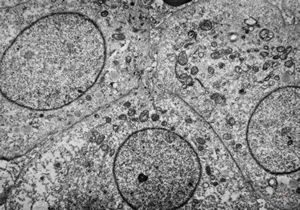

F,50y. | progressive multifocal leukoencephalopathy- viral particles in a glial cell